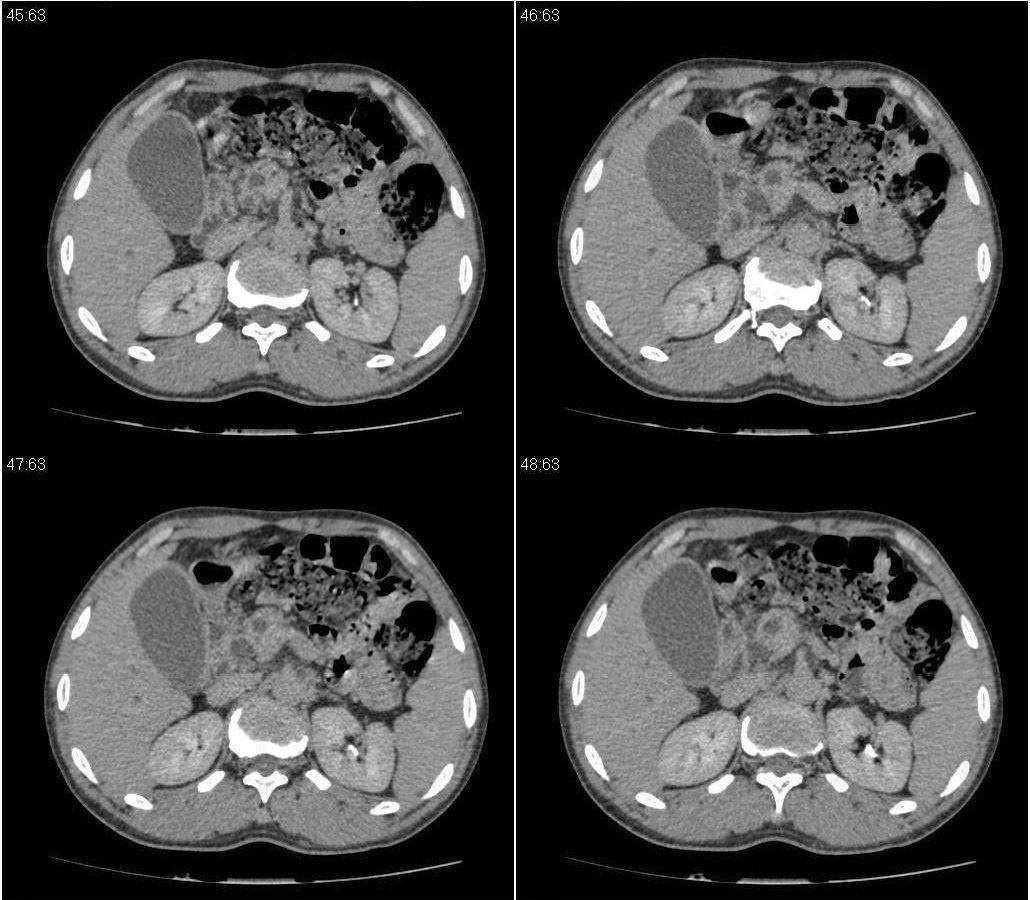

标题: CT21384:男性,50岁。发现无痛性黄疸十余天,B朝提示肝胆管 [打印本页]

标题: CT21384:男性,50岁。发现无痛性黄疸十余天,B朝提示肝胆管

1.考虑:壶腹占位病变(癌?)。

2.胆系低位梗阻:肝内外胆管扩张,胆囊增大,胰管扩张。

胆系低位梗阻:肝内外胆管扩张,胆囊增大,胰管扩.壶腹癌。

胆系低位梗阻(肝内外胆管扩张,胆囊增大,胰管扩张);考虑胰头癌或壶腹癌所致。

胆总管突然中断,壁增厚且强化,考虑胆总管癌可能性大伴胆系梗阻,胆囊炎

胆系低位梗阻(肝内外胆管扩张,胆囊增大,胰管扩张,钩突似有占位);考虑胰头癌